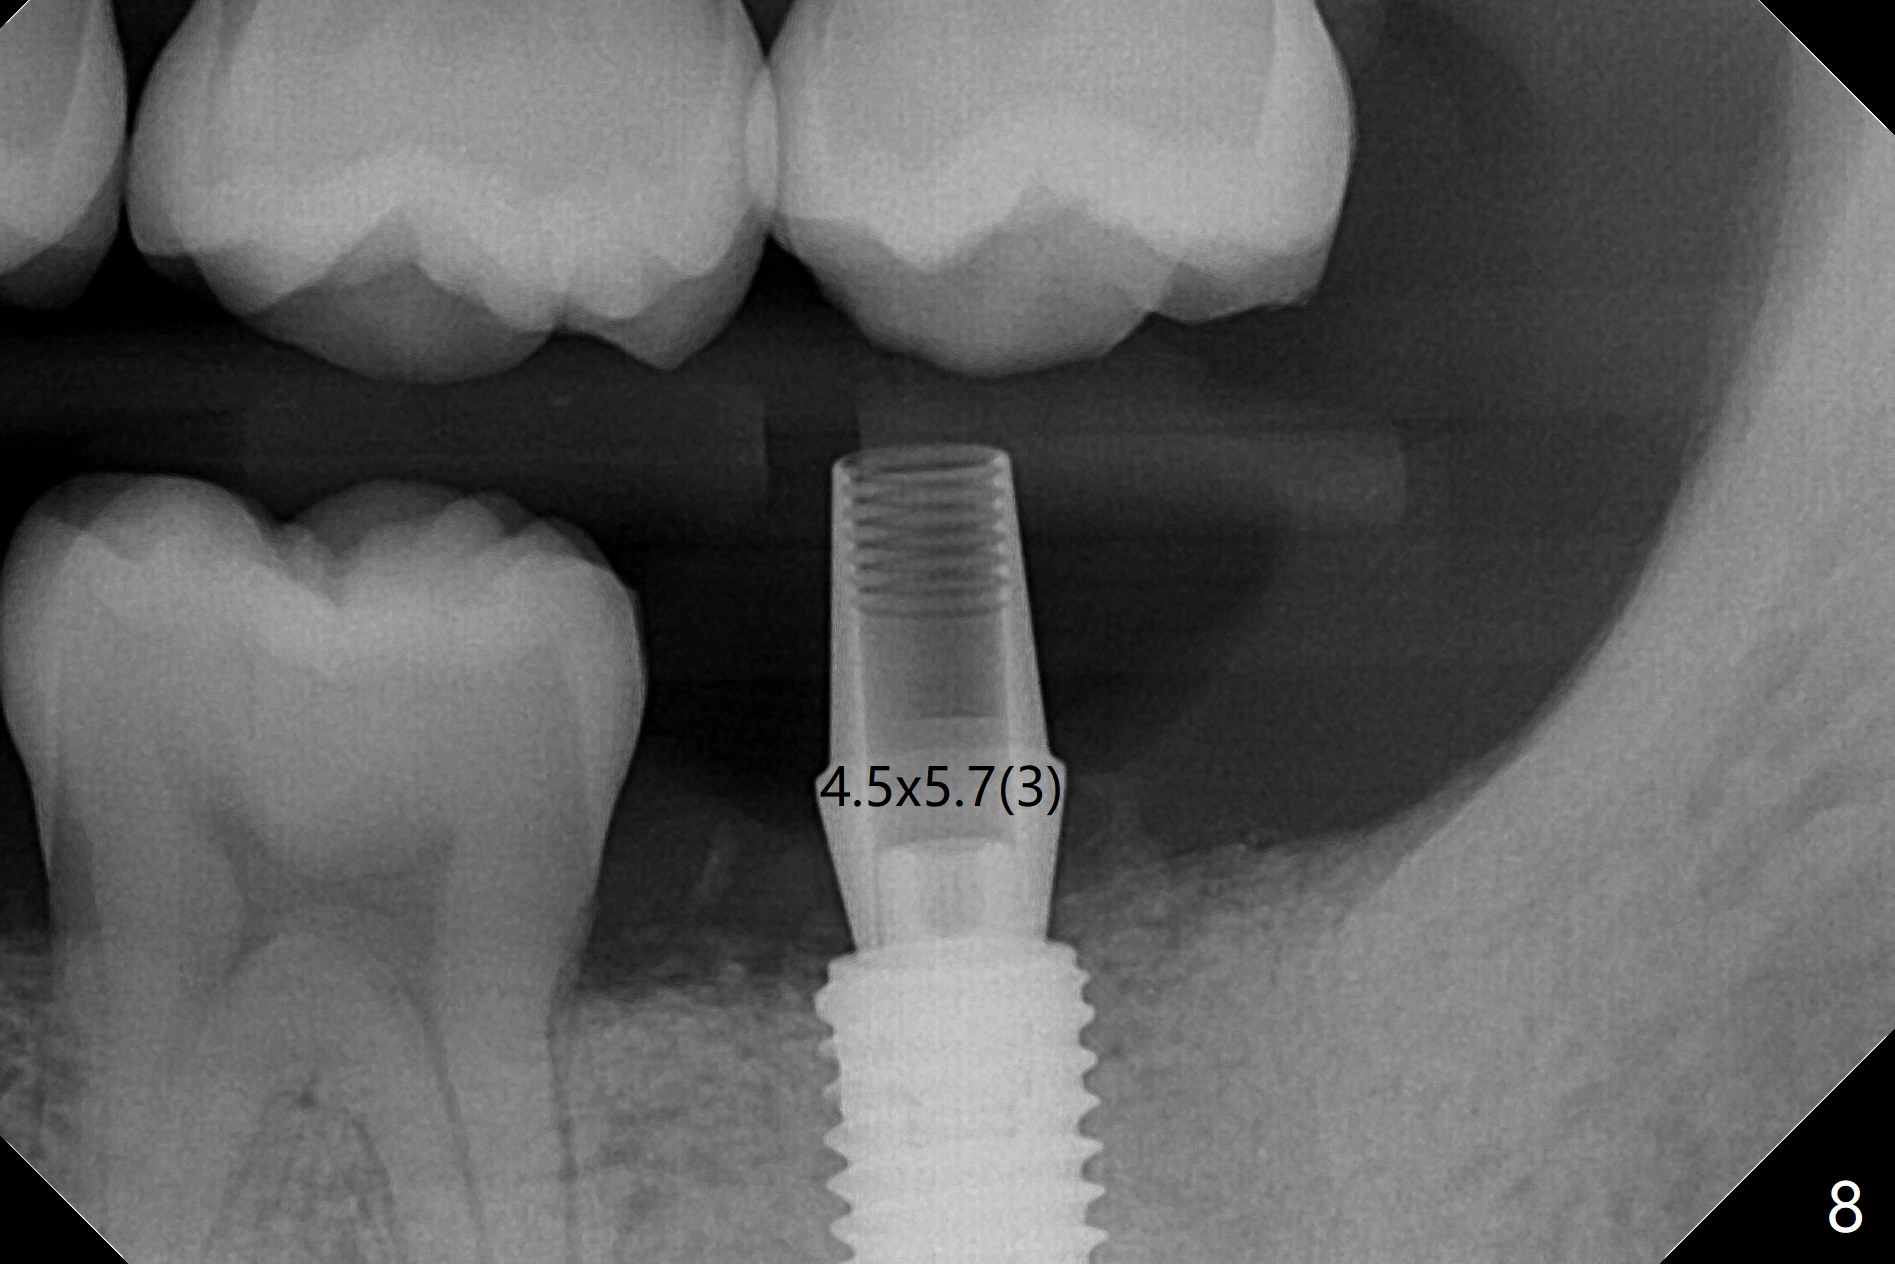

即刻种植即刻修复偶尔出现骨粉丧失,今天我们尝试临时基台,它可以制作像螺丝固位牙冠,可能会减少骨粉流失。左下7颊侧肿胀(图一:*),为了让植体(图二:绿色)植入中隔正中,钻洞时保留近中(M),远中(D)牙根。但是意想不到的是在导板指引下,钻头还是偏移近中(图三),而且颊侧(图四:圆圈),不过颊侧骨板没有缺损。由于牙根存在(硬),钻洞吃力,之后拔除,完成最后一个钻头,放置植体(图五),方位仿佛不错,临时基台(5.2x8(2)毫米)也完全就位,树脂围绕基台制作临时牙冠(图六),最后使用螺丝固位(*),颊侧肿胀牙龈必须用缝线固定(<),减少骨粉损失。由于牙冠与基台连接不好,病人汇报有些骨粉丢失。术后一个月检查尚可愈合正常,病人满意,已经做好思想准备做右下第二磨牙种植。临时牙冠进行修整。术后即刻近中牙槽窝间隙由粘性骨粉充填(图五),四个月后间隙消失(硬骨板也消失,图七),5.2x5(3)毫米粘固基台似乎没有完全就位,可能因为远中牙槽嵴阻挡(图七:*)。小一号基台仿佛完全就位(图八(咬翼片);图七(根尖片,可能失真)),但是临床上没有听到清脆声音(可能软硬组织阻挡)。随着时间推移,远中牙槽嵴吸收,当松动基台螺丝再次拧紧,可能会真正完全就位,必须拍摄完美咬翼片证实。这种植体芯(body, not threads)特别厚内部结构看不清楚。两周后粘固牙冠,然后取出牙冠和基台,清除残余粘固剂,然后复位,拧紧30Ncm。